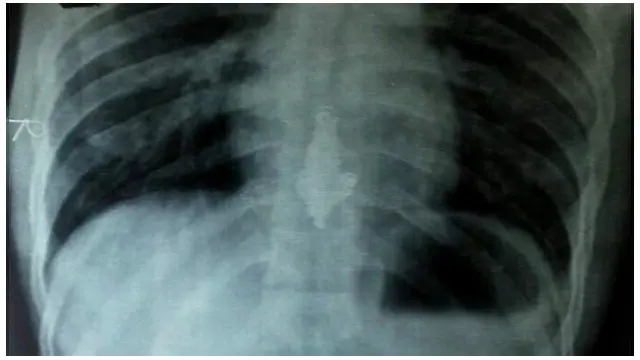

Dia diberikan makanan khusus setelah pemindaian sinar X tubuhnya menunjukkan kalung berada di dalam tubuhnya.

Kalung yang memiliki liontin besar tersebut sekarang sudah mencapai lambungnya.